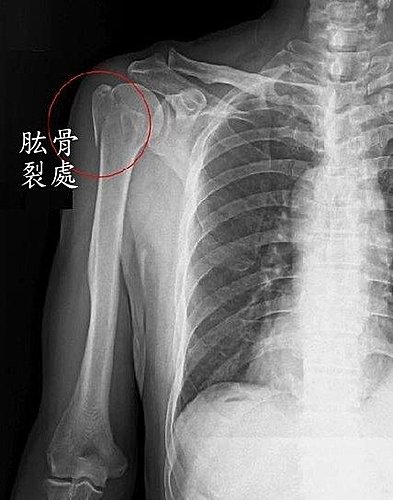

若淵肱骨斷裂處示意圖